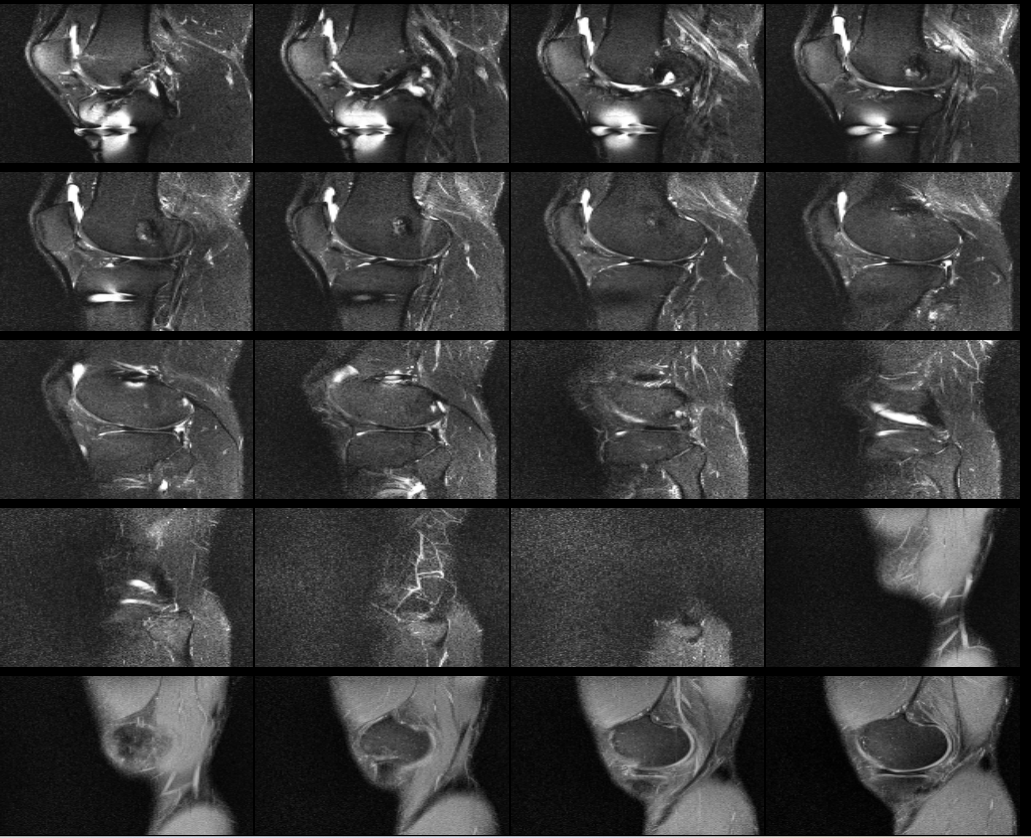

무릎 십자인대 재건술 후 약8년이 지난 지금 mri를 찍었습니다. 판독부탁드립니다ㅠㅠ

약 8년전 무릎 전방십자인대 재건술을 했는데 , 운동관련 직종이다 보니 , 운동을 많이 합니다.

최근들어 무릎에 불편한 통증이 있어 mri를 찍었는데 ,

활막염이라는 말만 들었는데 , 여러 선생님들의 의견을 듣고 싶어 사진올립니다. 판독해주시면 정말 너무너무

감사하겠습니다 간절합니다 ㅠㅠ

안녕하세요. 채홍석 의사입니다. MRI 퀄리티가 나빠서 판독은 어렵겠네요.

판독소견이 있으면 첨부해주시면 그건 해석해 드릴 수 있습니다.